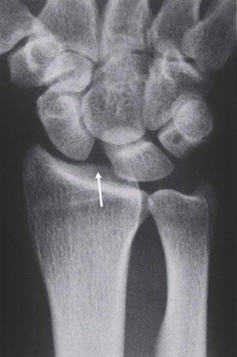

図2.SL靭帯損傷

舟状骨-月状骨間は解離している(矢印)

出典:中村 俊康 “手根骨間靱帯損傷, 手根不安定症とその治療.” *MB Orthopaedics* 32, no. 4 (2019): 79-84.